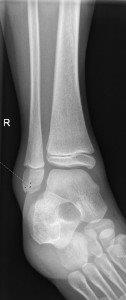

Avulsion fracture of distal fibula

Salter Harris I fracture of fibula

Undisplaced Salter Harris II fracture of fibula

Undisplaced epiphyseal fracture of distal fibula